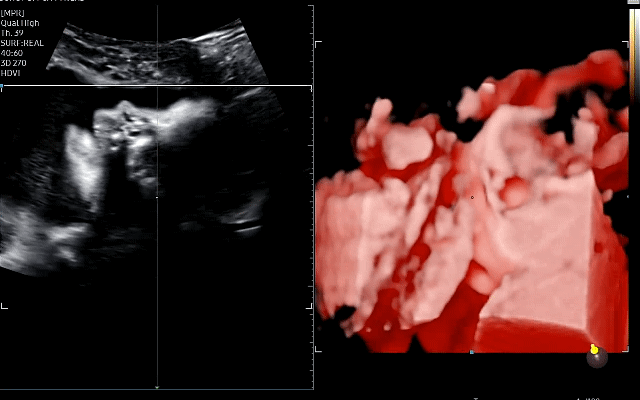

입체 초음파 - 두번째 시도만에 성공!

28주 초음파에서 내 등 방향으로 얼굴을 파묻어서 얼굴을 볼 수가 없었다.

결국 1차 시도는 실패!

하지만 얼굴을 파묻고 있는 너마저... 나는 너무 귀여운 것이야 엉엉

우리 딸은 항상 초음파를 보러가면 얼굴 쪽으로 손을 올리고 고뇌하고 있다..ㅎ

이 날은 고뇌를 넘어서 뭐가 그렇게 부끄러웠는지

양 손으로 얼굴을 가려버렸는데

저 째끄만 것도 손이라고 얼굴을 가려버리는게 너어어무 귀엽다!!